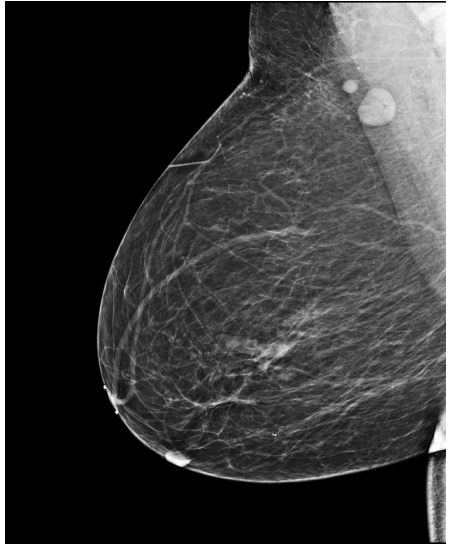

4.3 Pre-processing

The EMBED and CSAW-CC datasets originally consist of images in DICOM format, which are converted into 16-bit grayscale PNG images for consistency and compatibility. Following the pre-processing procedure outlined in (Yala et al.,, 2021), we enhanced image quality and removed background artifacts—such as textual annotations commonly present in mammography images—by applying a contour detection procedure. All contours in the image are detected, and only the largest contour, corresponding to the breast tissue, is retained. This contour is then used to create a mask that isolates the breast region from the background. The isolated breast image is resized to a size of 1664×20481664\times 2048 pixels while preserving the aspect ratio. Finally, the resized image is normalized and converted to a 16-bit format.

Following (Wang et al.,, 2024), we included only patients with at least five years of follow-up data for risk prediction. The datasets are randomly split at the patient level into training, validation, and test sets in a 5:2:3 ratio. Table1 presents the distribution of the Time-to-Cancer label and the dataset split for both the EMBED and CSAW-CC datasets.

For training the registration models (MammoRegNet), we randomly selected 1,000 patients from the risk prediction dataset, using two images per laterality and view combination. This selection method helps minimize training time and accommodate memory limitations. The dataset is then randomly split at the patient level into training, validation, and test sets, following the same 5:2:3 ratio.